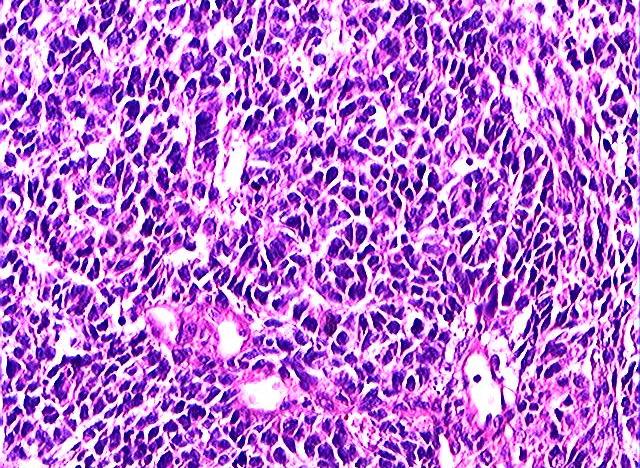

#国民医生说##健闻登顶计划##微博热点优质创作计划# 畸胎瘤是怀了“怪胎”吗?和胚胎发育有关吗?畸胎瘤并不是怀了 “怪胎”,它本质上是一种生殖细胞肿瘤,和正常胚胎发育没有直接关联,这是一个极易引发误解的医学概念。从病理本质来看,畸胎瘤是由胚胎时期的生殖细胞异常分化形成的肿瘤,而非真正的 “胎儿”。生殖细胞本应分化为人体的各类组织器官,但在发育过程中,部分细胞脱离了正常的分化轨道,在卵巢、睾丸等部位异常增殖,最终形成包含多种组织成分的肿瘤 —— 它可能含有毛发、牙齿、骨骼、油脂甚至少量神经组织,这些只是分化紊乱的人体组织,并非完整的胚胎或 “怪胎”。关于和胚胎发育的关联,需要区分两个层面:一方面,畸胎瘤的起源确实和胚胎阶段的生殖细胞有关,其发病根源是胚胎期生殖细胞的分化异常;但另一方面,它和母体的正常妊娠、胚胎孕育没有任何关系,既不是母体怀孕时形成的 “异常胎儿”,也不会因为怀孕而诱发或加重,未婚未育人群也可能患上畸胎瘤。另外,畸胎瘤多数为良性(成熟畸胎瘤),少数为恶性(未成熟畸胎瘤),良性畸胎瘤通过手术切除即可治愈,恶性类型则需结合病理分级进行后续治疗,总体预后相对较好,无需因 “畸胎” 的名称产生过度恐慌。